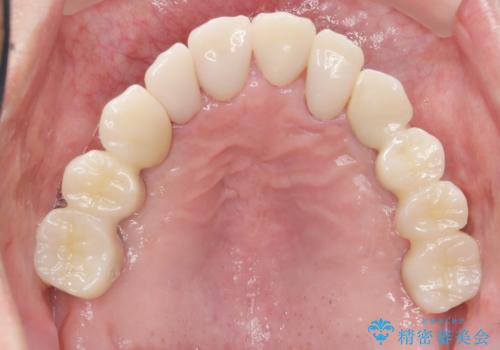

しっかりと咬むことができるようになり、喜んで頂けました。

他院ではお断りされたインプラント治療を行うことができ、ご満足頂けました。

被せ物の種類:オールセラミッククラウン ベレッツァ